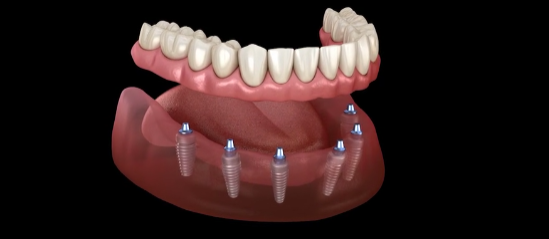

治療方案二

植牙支持式活動假牙

此方式是在上顎植入 4 顆植體,下顎植入 2–4 顆植體,

再將可拆卸式假牙牢固地固定於植體之上。

植牙支持式活動假牙能解決傳統假牙常見的不便,

如

鬆動、進食時滑動、佩戴不適 等問題,

同時相比傳統全口植牙,大幅降低費用負擔。

這是一種

兼具經濟性與穩定性 的治療選擇,

能有效提升生活品質。